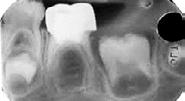

Estudios radiográficos de inicio en la radiografía lateral de cráneo (Figu ra 5) tenemos la clase II esquelética con un ANB de 7°, hiperdivergencia, aumento de la altura facial anterior, disminución de la altura facial poste rior y proclinación del incisivo supe rior con 1 a plano palatino de 121° e incisivo inferior de 1 a plano mandi bular de 99°.

En la radiografía panorámica (Figu ra 6) se observan 32 dientes, con los terceros molares en formación, adicionalmente la molar 46 con una

Figura 6. Radiografía panorámica inicio.

Corrección de mordida abierta anterior por deglución atípica Figura 5. Radiografía lateral de cráneo inicio.